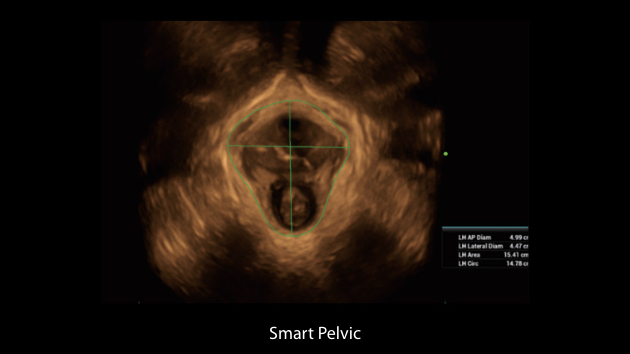

Obrazy kliniczne